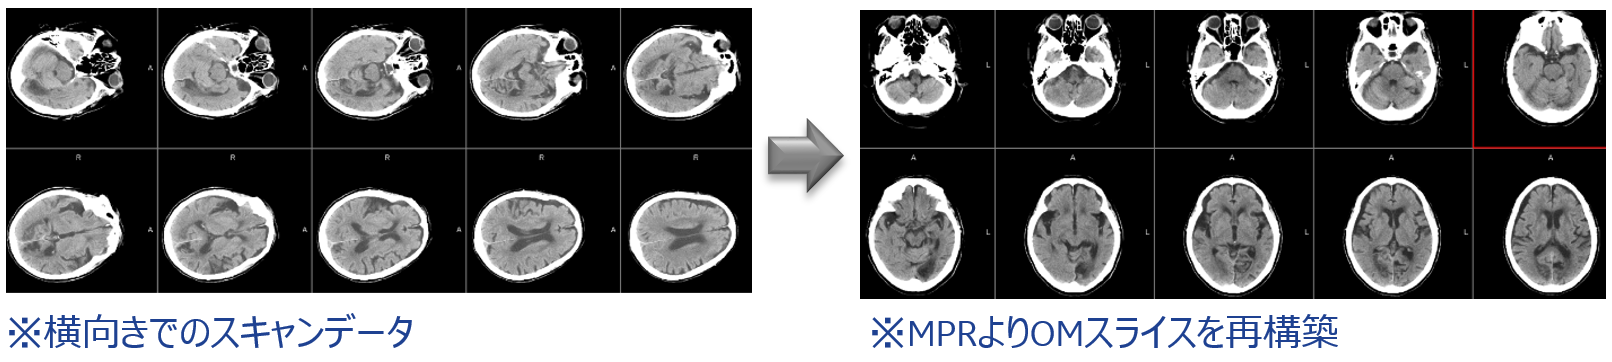

従来のチルトコンベンショナルスキャンによる頭部検査では、脳底部、特に脳幹、小脳付近の画質はあまり良いとは言えませんでした。それがRevolution ACTでは、1.25mmスライスでのヘリカルスキャンができるので、薄いスライスでの収集による効果でアーチファクトが軽減され、また連続したデータであることからMPR(サジタル面、コロナル面)での画質が格段に向上しました。その結果、小脳、脳幹部の診断への信頼度が上がり、また、海馬領もコロナル面での観察が容易にでき、臨床有用性を高めています。

cv_uchida_04_big.png

また、横向きでしかスキャン体位を取れない患者様の場合でも、Revolution ACTでは、そのままスキャンを行い、検査終了後に画像をOMスライスに変換できるため、患者様の負担を大幅に軽減できることができました。

cv_uchida_05_big.png